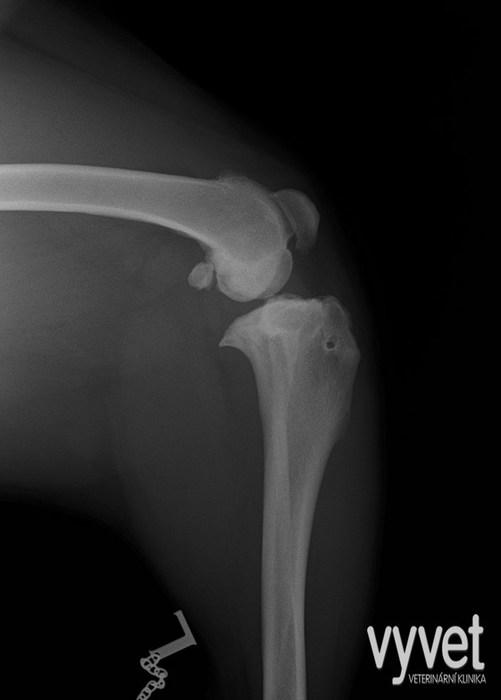

Jedná se o postupně se vyvíjející proces, který může být příčinou vážných komplikací při chůzi. Pacient, který má tento problém a jehož majitelé jej z mnoha důvodů nechtějí řešit, je odsouzen ke vzniku vážných komplikací. V kolenním kloubu narůstá výrazná artróza. Jsou více zatížené zkřížené vazy, které ve středním věku pacienta často praskají. (další info.viz ruptura zkřížených vazů)

Ruptura zkříženého vazu je velmi častým onemocněním psů středních a velkých plemen. Jedná se o akutní, velmi bolestivé onemocnění doprovázející intenzivní kulhání. Nejčastěji se vyskytuje u psů středních a velkých plemen. Popsáno je u všech hmotnostních kategorií. U malých psů vzniká často sekundárně, ve spojitosti s luxací čéšky.

Nitro kloubní fraktury jsou pro pacienty všeobecně výrazně bolestivější než fraktury dlouhých kostí a z toho vyplývá i doba hojení a rekonvalescence po zákroku.